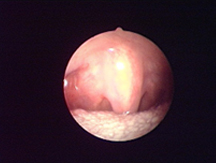

全新SURGITRON DUAL RF 120IEC,擁有更美的外觀,更強(qiáng)的性能,優(yōu)越的射頻止血功能,作為同時(shí)擁有4.0 Mhz和1.7Mhz的雙射頻產(chǎn)品,能應(yīng)用于更多的科室手術(shù)。